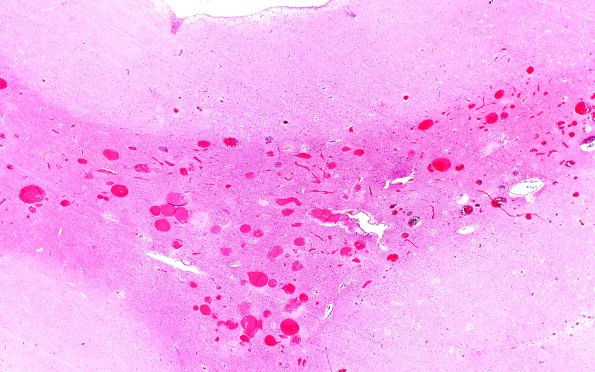

28B2 Telangiectasis (Case 28) H&E 3

A section of cortex shows the composition by large numbers of dilated thin walled vessels with a uniform composition (H&E).